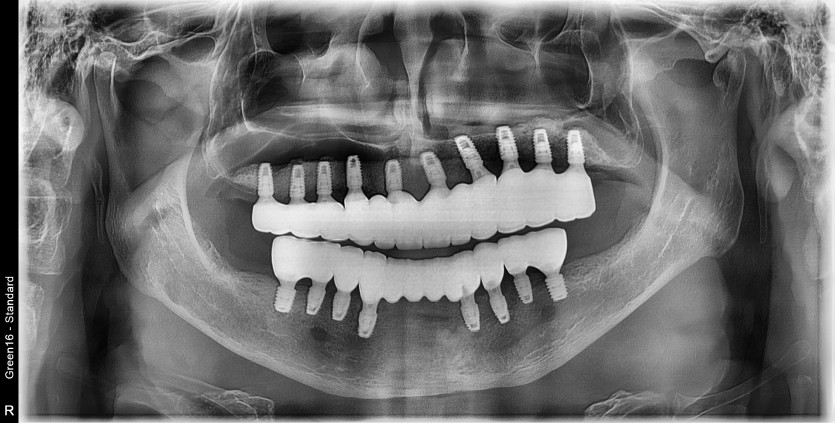

만 55세 전체 임플란트 증례

전체 임플란트 증례입니다.

18개의 임플란트로 완성하였습니다.